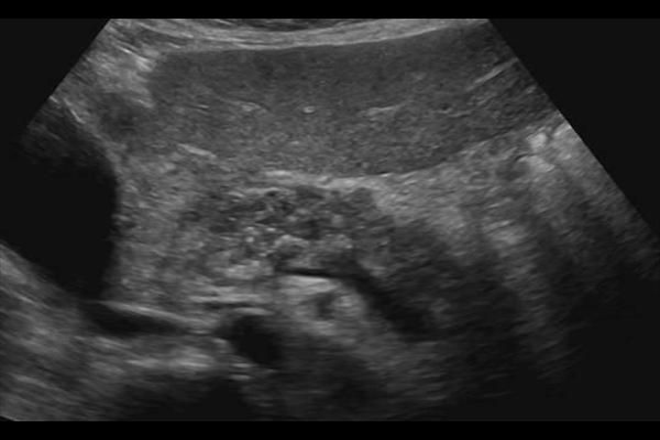

Utilidad de la ecografía transabdominal contrastada para el diagnóstico temprano de pancreatitis crónica.

Estudios recientes han demostrado que la vascularidad con la ultrasonografía  transabdominal contrastada mejorada (CEUS) se correlaciona con el grado patológico de  fibrosis en pacientes con pancreatitis autoinmune y CP.

Especulamos que CEUS usando perflubutano podría desempeñar un papel clave en la clasificación del grado de la CP. El propósito de este estudio fue establecer la relación entre el grado de pancreatitis crónica y el flujo sanguíneo pancreático, medida por CEUS.

Hemos demostrado la relación del flujo sanguíneo observado por CEUS correlacionado con la progresión de la CP. Schilling et al. informaron que el flujo de sangre del páncreas fue disminuido significativamente en los pacientes con CP. Del mismo modo, un estudio histológico por Angelis et al. encontraron que la fibrosis del páncreas y los cambios en los vasos sanguíneos se observaron en el 80-100% y 14-44% de los pacientes con CP, respectivamente. Hemos demostrado que el flujo de sangre en el páncreas disminuye de una manera escalonada concordante con estos criterios, y CEUS puede así ofrecer un método útil para clasificar el grado de CP.

La ecografía transabdominal contrastada se demostró que es una herramienta útil para la valoración de pancreatitis crónica y la correlación existente entre la vascularización del mismo, con la finalidad de en un futuro tratar de prevenir la fibrosis en una pancreatitis crónica. Por lo cual hoy en día la ecografía va abarcando un gran amplio campo, con el cual se va a poder dar solución o dar continuidad a distintas enfermedades tanto como medicamente, económicamente y hasta en tiempo.